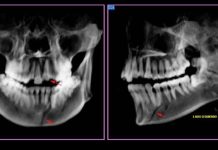

La víctima quedó internada en observación.